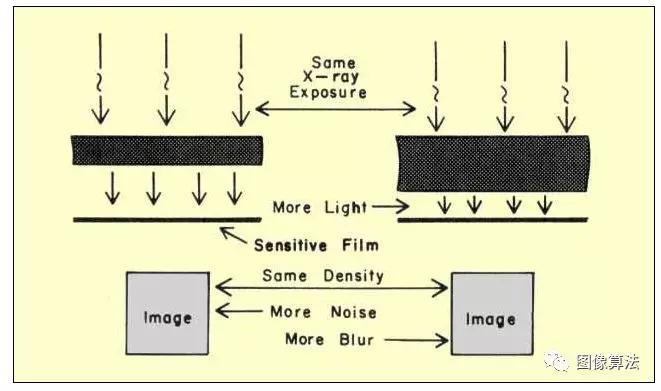

形成图像所需的受体暴露(受体敏感性)可以通过修改几个因素来改变,如下图所示。图中右侧所示的薄膜灵敏度决定了产生所需薄膜密度所需的光量。如果增加胶片的灵敏度以减少所需的光量,反过来,这将减少必须在屏幕中吸收的X射线光子的数量。结果将是具有增加的量子噪声的图像。回想一下,特定胶片和屏幕组合的有效灵敏度取决于胶片的光谱灵敏度特性与屏幕产生的光的光谱特性的匹配。当两个特征紧密匹配时,产生最大灵敏度和最大量子噪声。在射线照相术中,改变胶片的灵敏度(即改变胶片的类型)是调节图像中量子噪声水平的最直接方法。量子噪声通常是限制在射线照相中使用高灵敏度薄膜的因素。

强化屏 - 膜受体内辐射量的关系

具有相同灵敏度的两种屏幕 - 胶片组合如下所示。一种系统使用相对较厚的高速屏幕和具有传统灵敏度的薄膜。另一个系统使用更细的细节速度屏幕和更敏感的电影。这两个系统产生的图像在两个方面有所不同。与使用更敏感的胶片的系统相比,使用更厚屏幕的系统具有更多模糊但更少的量子噪声。噪音的 减少来自 吸收效率的提高和 模糊的增加。

两种丝网膜组合的图像质量比较